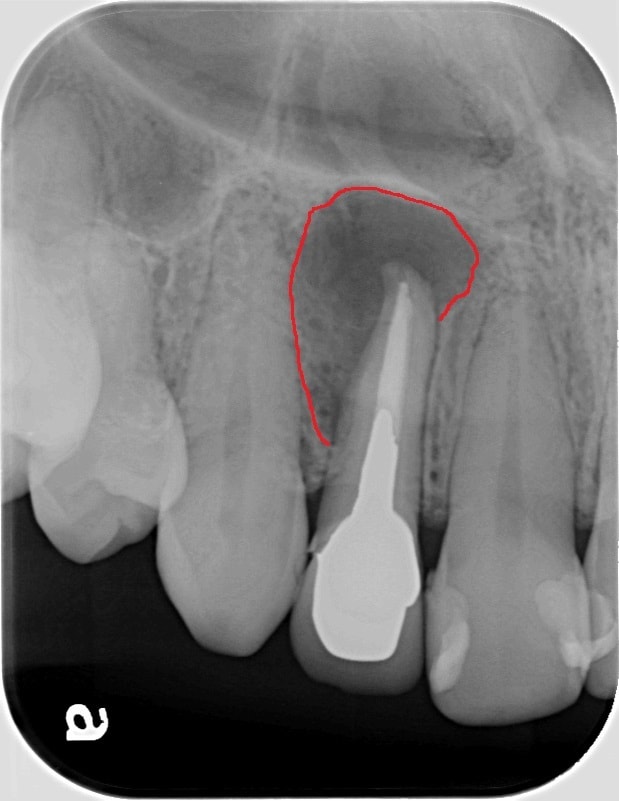

治療前

治療前の赤い線で囲まれた部分が簡単に言うと、骨が溶かされている部分で、

状態の余り良くない部分になります。

様々なことを総合的に考えて、MTAセメントを用いて歯根端切除術という手術を行いました。

1年7ヶ月後のレントゲンで、緑の線で囲まれている部分が小さくなってきているのがわかると思います。歯の周りに骨が再生してきていると思われます。これから経過をしっかり追っていく必要はあるかと思いますが、取り合えず一安心です。